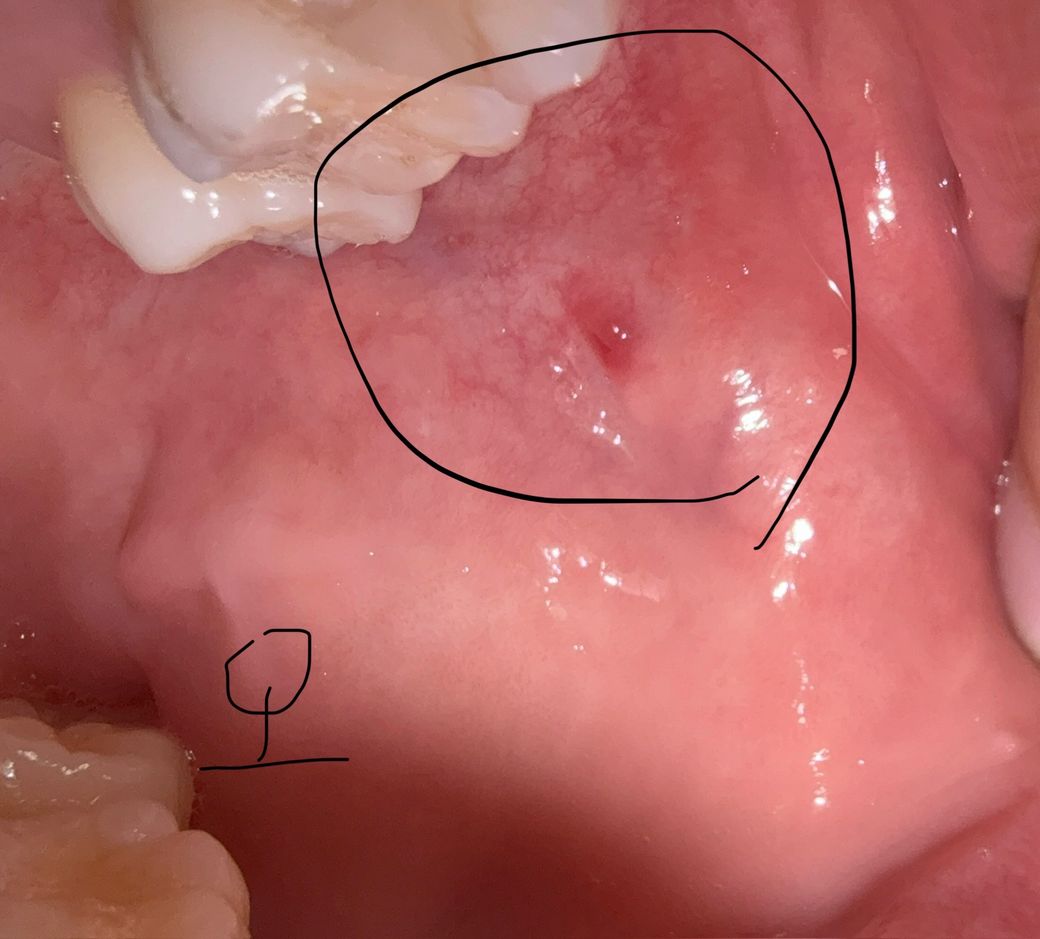

구강암 의심해도 되는지 봐주세요ㅠㅠ

한달 반 정도 부터 볼쪽에 혀로 만졌을때 염증같은 느낌이 나는데 특별한 통증은 없는데 이게 생긴뒤로 혓바늘이 자주나고 가끔 오른쪽 아래턱뼈가 저리는 느낌을 받고 침 삼킬때 목에 가시걸림 느낌도 있는거 같고 여러모로 불안한 마음에 올려봅니다ㅠㅠ 또 병원을 가서 검사를 한다면 무슨병원을 가야할지 알려주시면 감사하겠습니다.

• 2번 째 사진

병소 양상이 경계가 명확하고 출혈성도 아니고, 경결감도 보이진 않으므로 악성 가능성은 낮습니다 구강내과가서 추가적인 진단 받아보세요